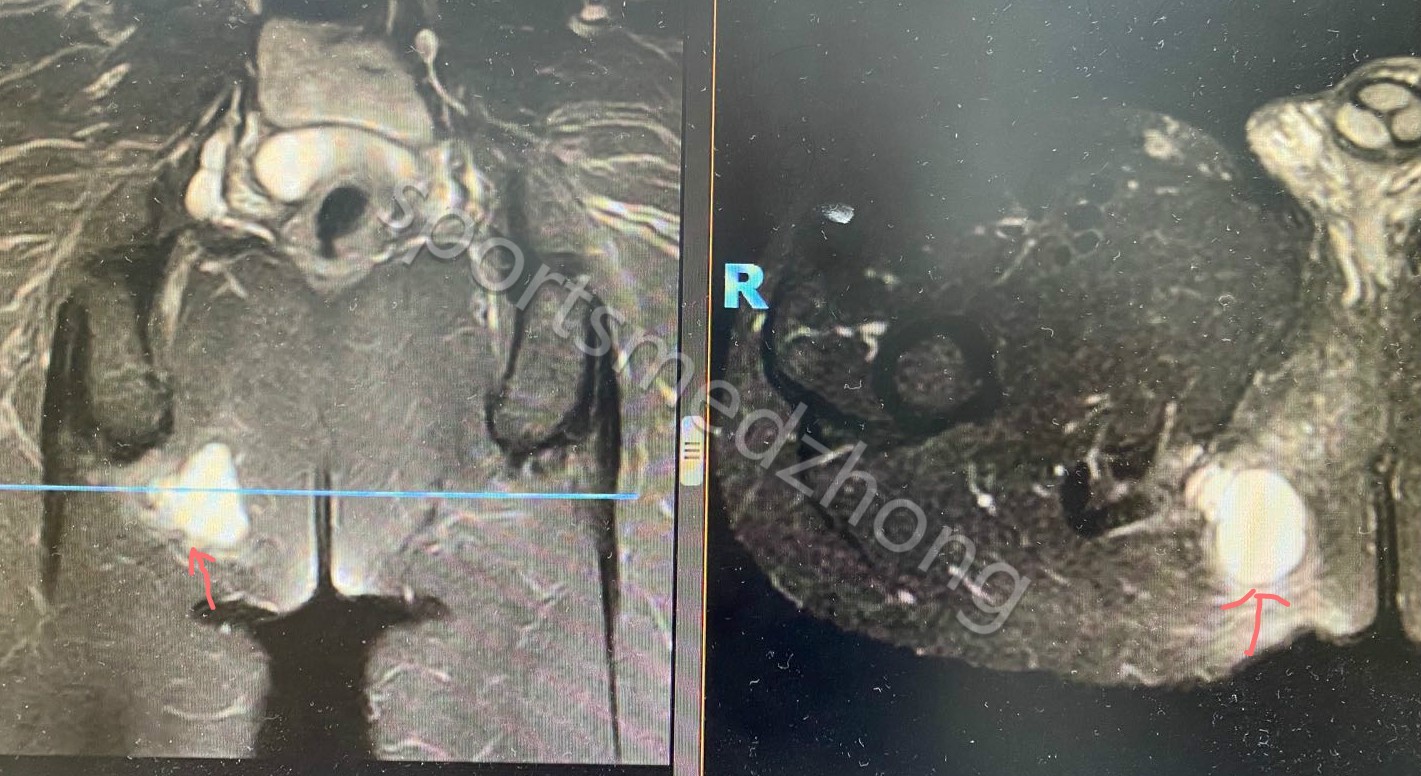

3. B超作为经济快捷的检查方法可以快速准确的发现坐骨结节旁的囊性包块(图2);MRI 可以显示坐骨结节囊肿大小、位置及与周围结构的关系(图3)

图3 MRI 可以显示坐骨结节囊肿大小、位置及与周围结构的关系